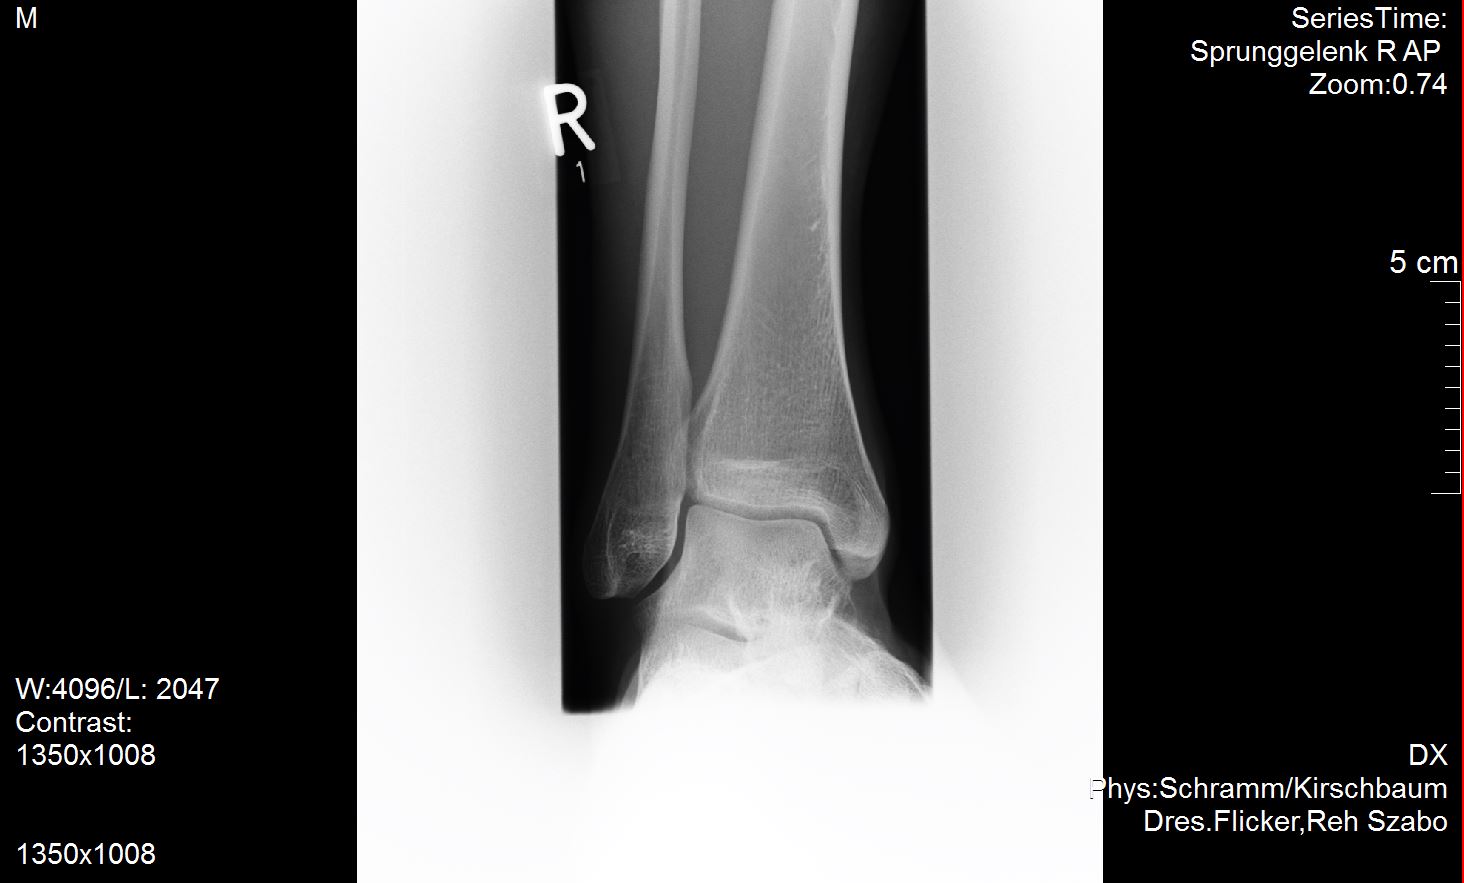

Ich versuche mal meine Röntgenbilder anzuhängen. Vielleicht ist ja ein Experte unter uns der dazu was sagen kann?

Ich habe außer dem mir diagnostizierten Spreizfuß nach oben stehende Zehen. Weiß nicht genau ob man dies Hammerzeh oder Krallenzeh nennt was ich habe aber es geht in die Richtung.